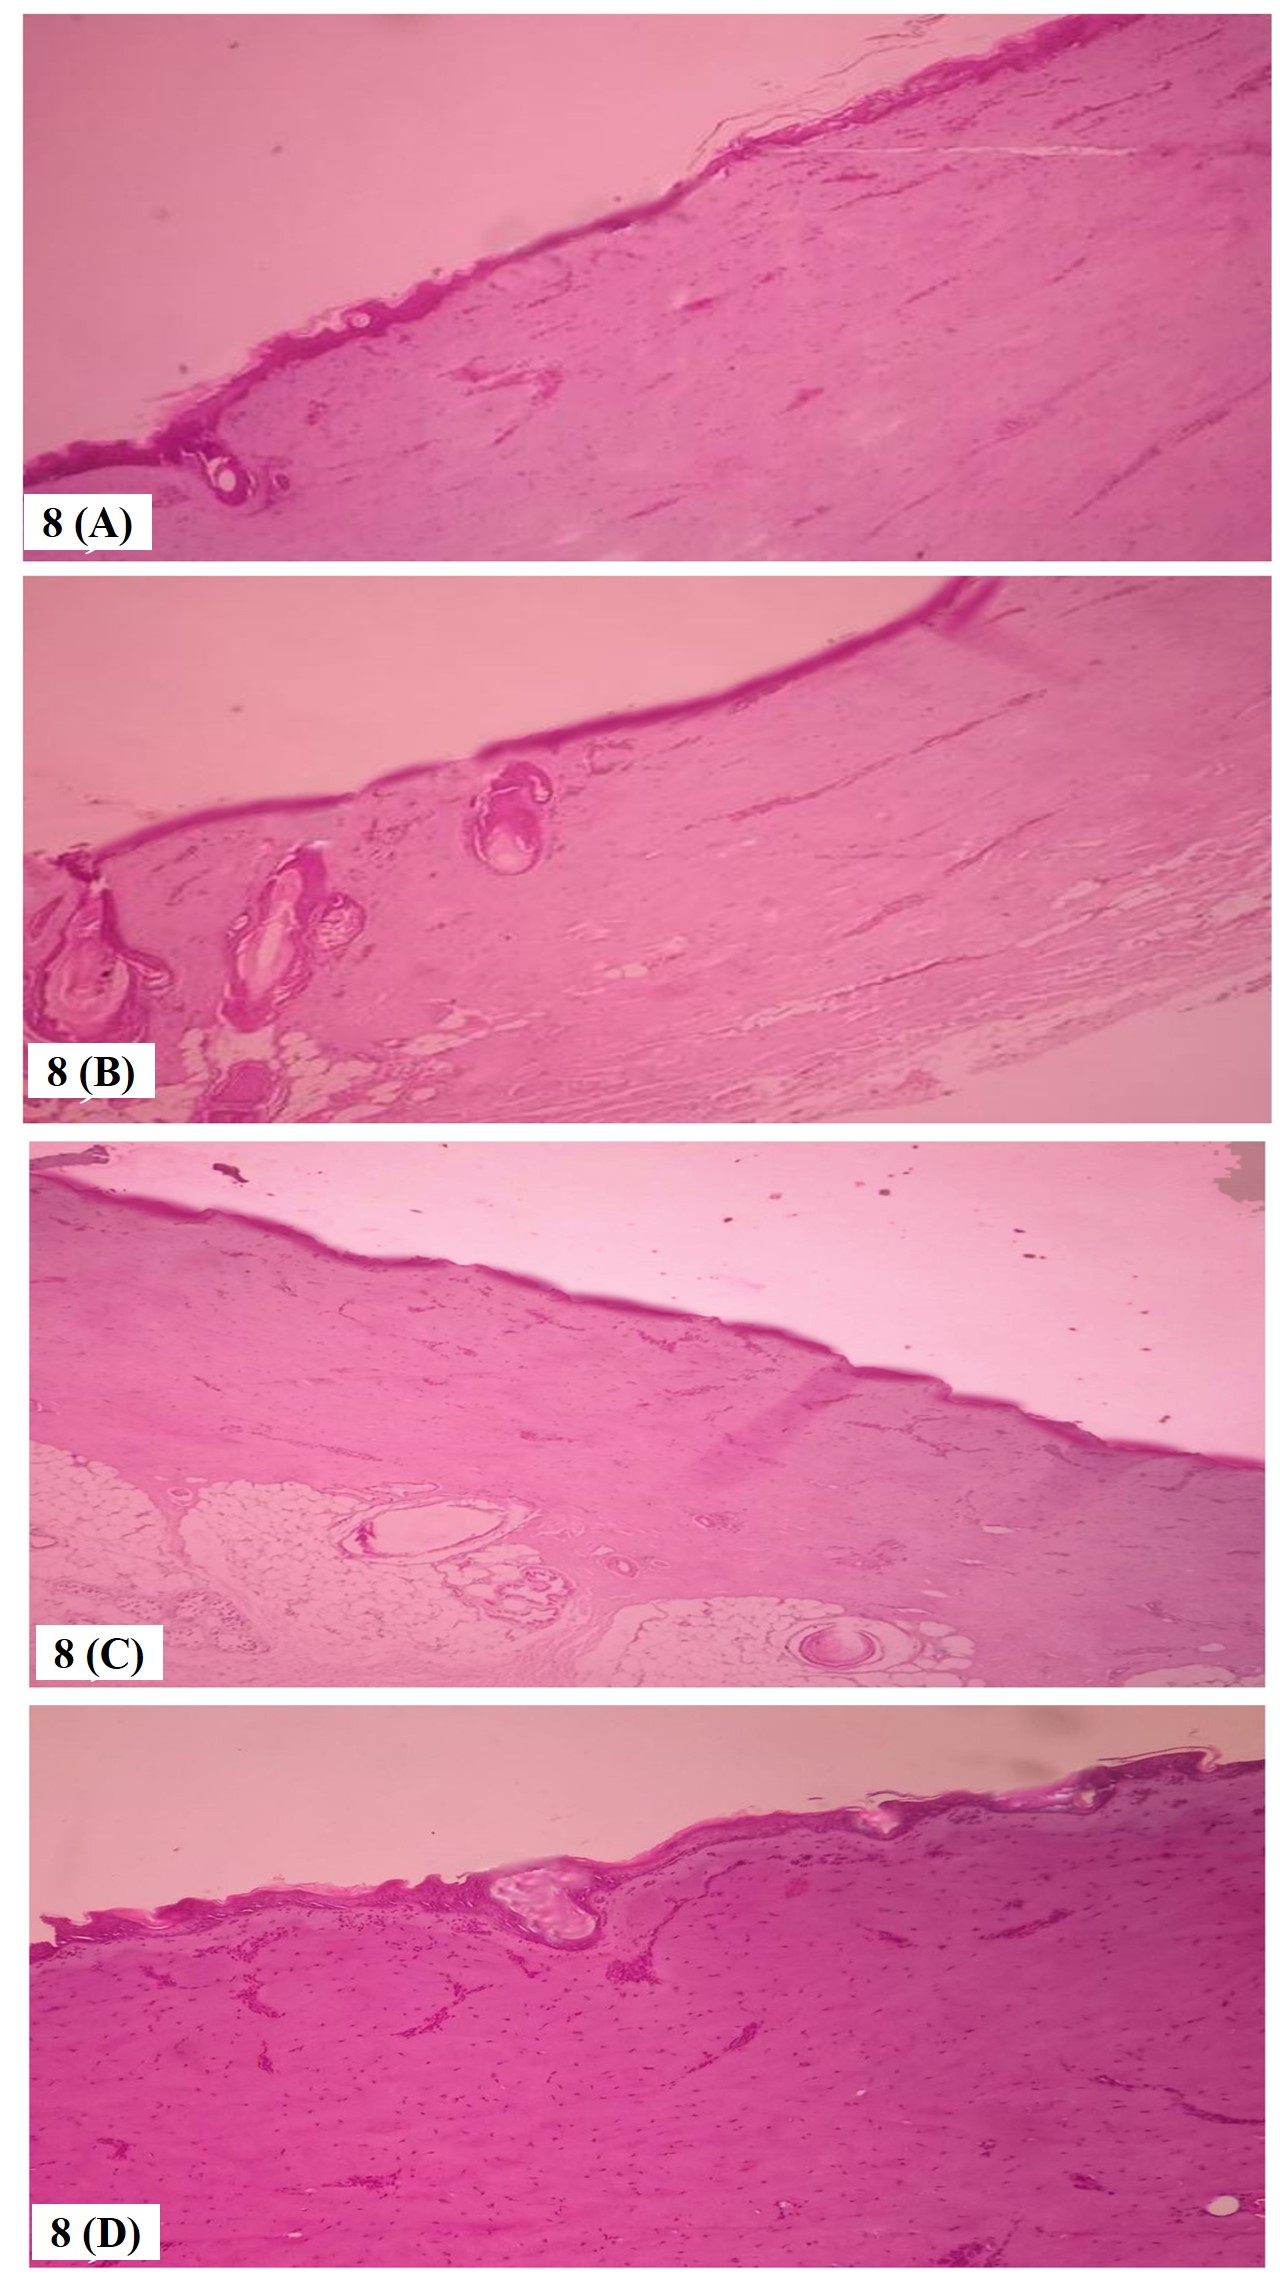

Fig. 8: Histopathological evaluation of porcine skin. 8(A) Porcine skin treated with midazolamloaded niosome N5, 8(B) Porcine skin treated with midazolamloaded niosomal transdermal patch, 8(C) porcine skin treated with control (Drug in buffer solution), 8(D) Normal porcine skin

Histopathological examination

The porcine mucosa subjected to ex vivo permeation studies were assessed for histopathological changes [92]. The fig. 8(A),(B),(C) shows that neither the optimized midazolam loaded niosome (N5), optimised midazolam loaded niosomal transdermal patch (NT5) and drug loaded in buffer solution PBS pH 5.5, shows no significant changes in the histological pattern when compared to normal mucosadepicted in fig. 8 (D). Hence the midazolam loaded niosomal transdermal patch does not cause any irritation and is safe for transdermal application [93].